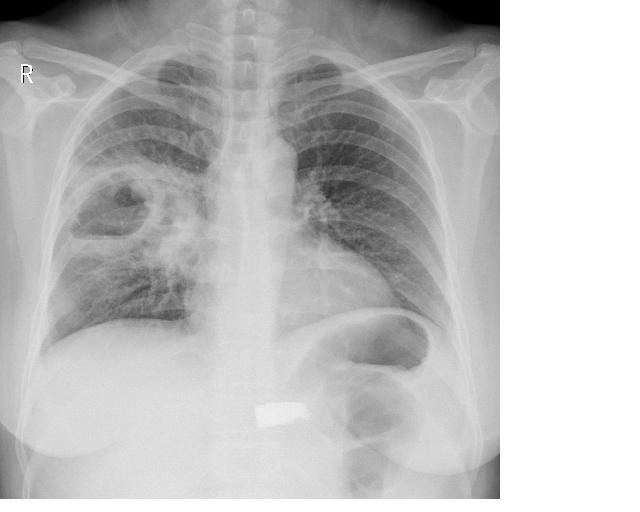

男,成人,因咳嗽、右胸痛拍片。

厚壁空洞+液平+周围感染 支持 右下肺脓肿

如果是抗炎治疗后查:病灶明显减小。支持肺脓疡。